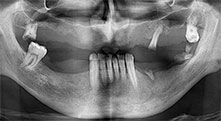

Bratu: We routinely use the instruments for harvesting bone blocks and splitting alveolar ridges. We also use the Piezomed B6/B7 for osteotomy of impacted teeth and removing failed implants. All indications that require deep, clean cuts.

Bratu: We prefer to harvest bone from the external oblique ridge of the posterior mandible, not from the interforaminal region. After the soft-tissue incision, we use the new saws to define the amount of bone to harvest. With this approach, we also use them for the entire preparation in almost 80% of cases. We may also use other piezo instruments and then at the end a chisel to mobilize the block. We find that this is a very effective surgical technique.

Bratu: We like to use the sandwich technique for augmentation in the lateral mandible. A bone cover is prepared with the piezo saw and the crestal fragment is fixed with microscrews. We place a mixture of autologous bone and xenogenic bone replacement material in between. This works very reliably. You should always ensure sufficiently dimensioned vertical cuts when splitting the alveolar ridge in the mandible. Otherwise the bone may fracture easily.

Bratu: I consider piezo surgery a great leap forward in oral surgery. The technique makes bone preparation safer and easier. Little bone is lost, for example in extractions. This is very important in the aesthetic zone, particularly if immediate implantation is planned. Piezo surgery is also safer for soft tissue: injuries to membranes in the sinus are basically history, as are nerve injuries when bone blocks are being harvested. Data indicating reduced postoperative swelling and pain are also available. Piezo surgery is also ideal for preparation of sinus septa. And last but not least, our patients benefit from the atraumatic nature of this technology.